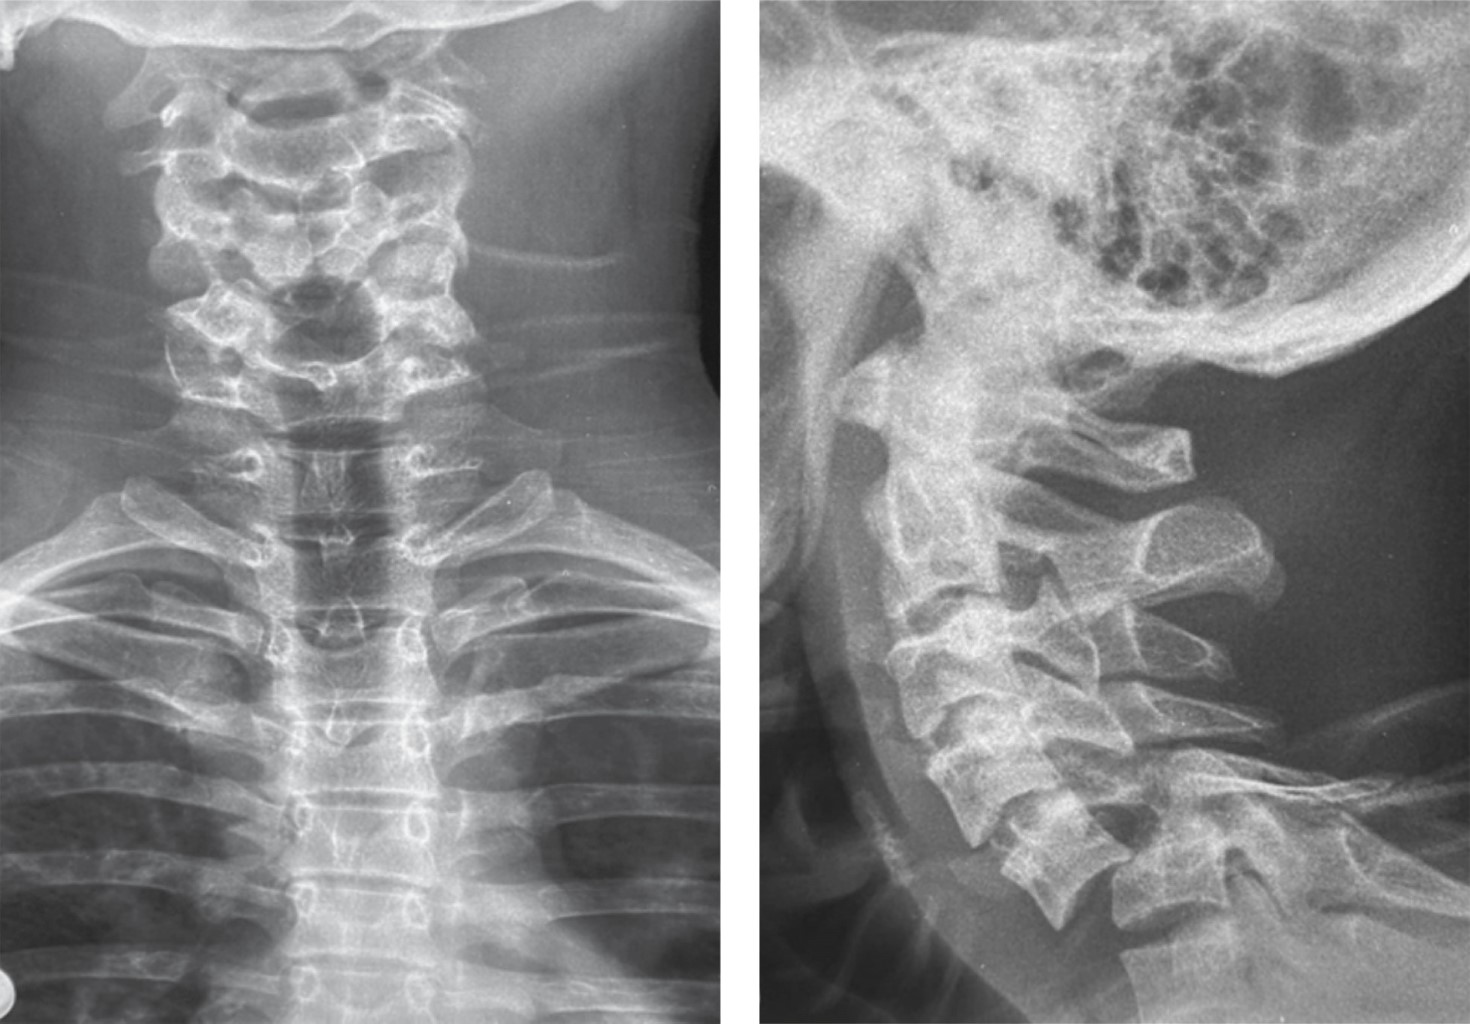

Introducción: la luxación cervical subaxial es una grave lesión, usualmente debido a un trauma de alta energía. El manejo es controvertido, más aún cuando el cuadro neurológico está intacto. Tener los estudios necesarios para evaluar el método de reducción (abierto o cerrado), así como la mejor opción de abordaje (anterior, posterior o 360°). Presentación de caso: paciente masculino de 19 años con historia de accidente de motocicleta, asistido en Hospital Regional de Petén, Guatemala. El examen neurológico evidencia función sensitiva y motora completa, radiológicamente (rayos X y tomografía) con fractura luxación C5-C6. Paciente fue inmovilizado y transferido a nuestro centro hospitalario. Al ingreso, se le realiza tracción esquelética con peso de 12 kg, con obtención de reducción parcial. Posteriormente, se realizó una instrumentación mediante abordaje posterior de C3-C7, el paciente evolucionó con adecuada función neurológica. Conclusión: el manejo de las luxaciones subaxiales sigue siendo controversial, especialmente en pacientes con un cuadro neurológico estable. La evaluación clínica adquiere un papel fundamental en centros hospitalarios sin acceso a resonancia magnética, ya que la reducción cerrada puede ser una opción efectiva siempre que se acompañe de una vigilancia neurológica continua. Asimismo, el abordaje posterior permite favorecer la cicatrización de los elementos posteriores y facilita la evaluación futura para un posible retiro del material, considerando la preservación de los discos intervertebrales.

Figura 3